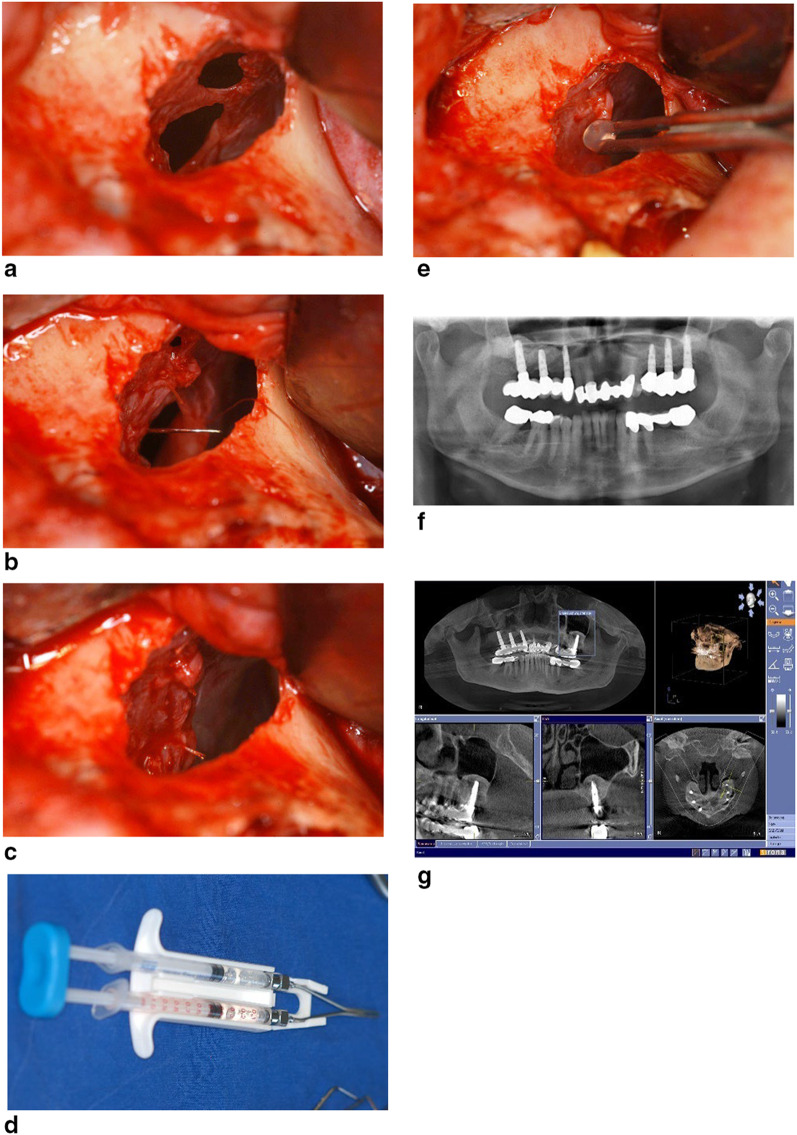

The sinus lift procedure has become the most common method for maxillary bone augmentation. The most frequently observed intraoperative complication is the perforation of the Schneiderian membrane. Various treatment options have been proposed for managing these perforations, including the use of resorbable membranes, centrifugated blood products as PRF, or PRGF, suturing, and fibrin glue application. While long-term studies exist for the use of resorbable membranes to close perforations, there is limited data on the long-term outcomes of suturing or gluing the perforated sinus membrane. The aim of this retrospective study is to evaluate the long-term outcomes of suturing and/or applying fibrin glue to repair perforated sinus mucosa during sinus floor elevation procedures. Between 2005 and 2009, a total of 692 patients underwent 923 sinus lift surgeries, and Schneiderian membrane perforation occurred in 202 sinus floor elevations (21.98%) across 168 patients. The main documented causes of perforations, which ranged from 2 to 10 mm in diameter, were the presence of septa, followed by thin and adherent membranes. Of the perforations, 100 (49.5%) were treated with microsurgical suturing combined with fibrin glue, 78 (38.6%) were treated with fibrin glue alone, and 24 (11.9%) were treated exclusively with suturing. Sinus grafting was performed using autogenous bone in combination with a biomaterial, following the layering technique. All surgeries resulted in primary healing without complications, enabling all patients to undergo restoration as planned. The long term clinical and radiological evaluations of 44 randomly selected patients who followed the recall program up to 10 years post operative confirmed the effectiveness of this treatment approach.